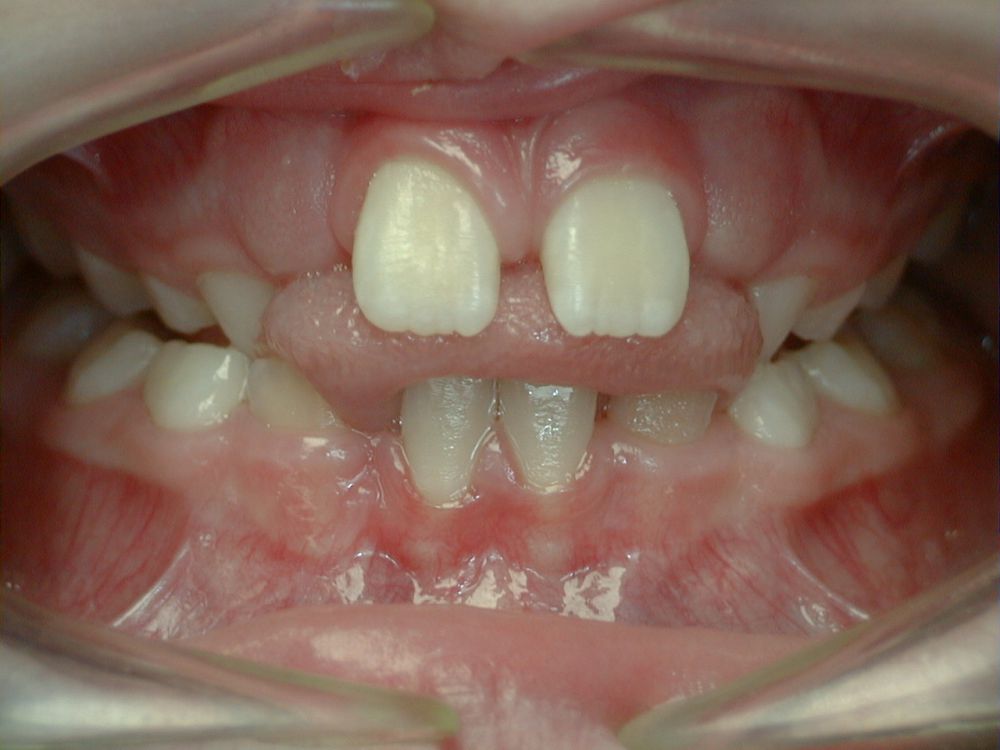

La déglutition

La déglutition est l'acte d'avaler la salive ou les aliments. Cet acte est répété plus de 2500 fois par 24 heures. Ainsi une mauvaise déglutition peut très bien expliquer une mauvaise position des dents et un mauvais développement des mâchoires.

Education fonctionnelle

Pour une bonne croissance, il est indispensable que les fonctions (respiration, déglutition, mastication, phonation et posture) soient correctes. C'est le rôle de l'éducation fonctionnelle.